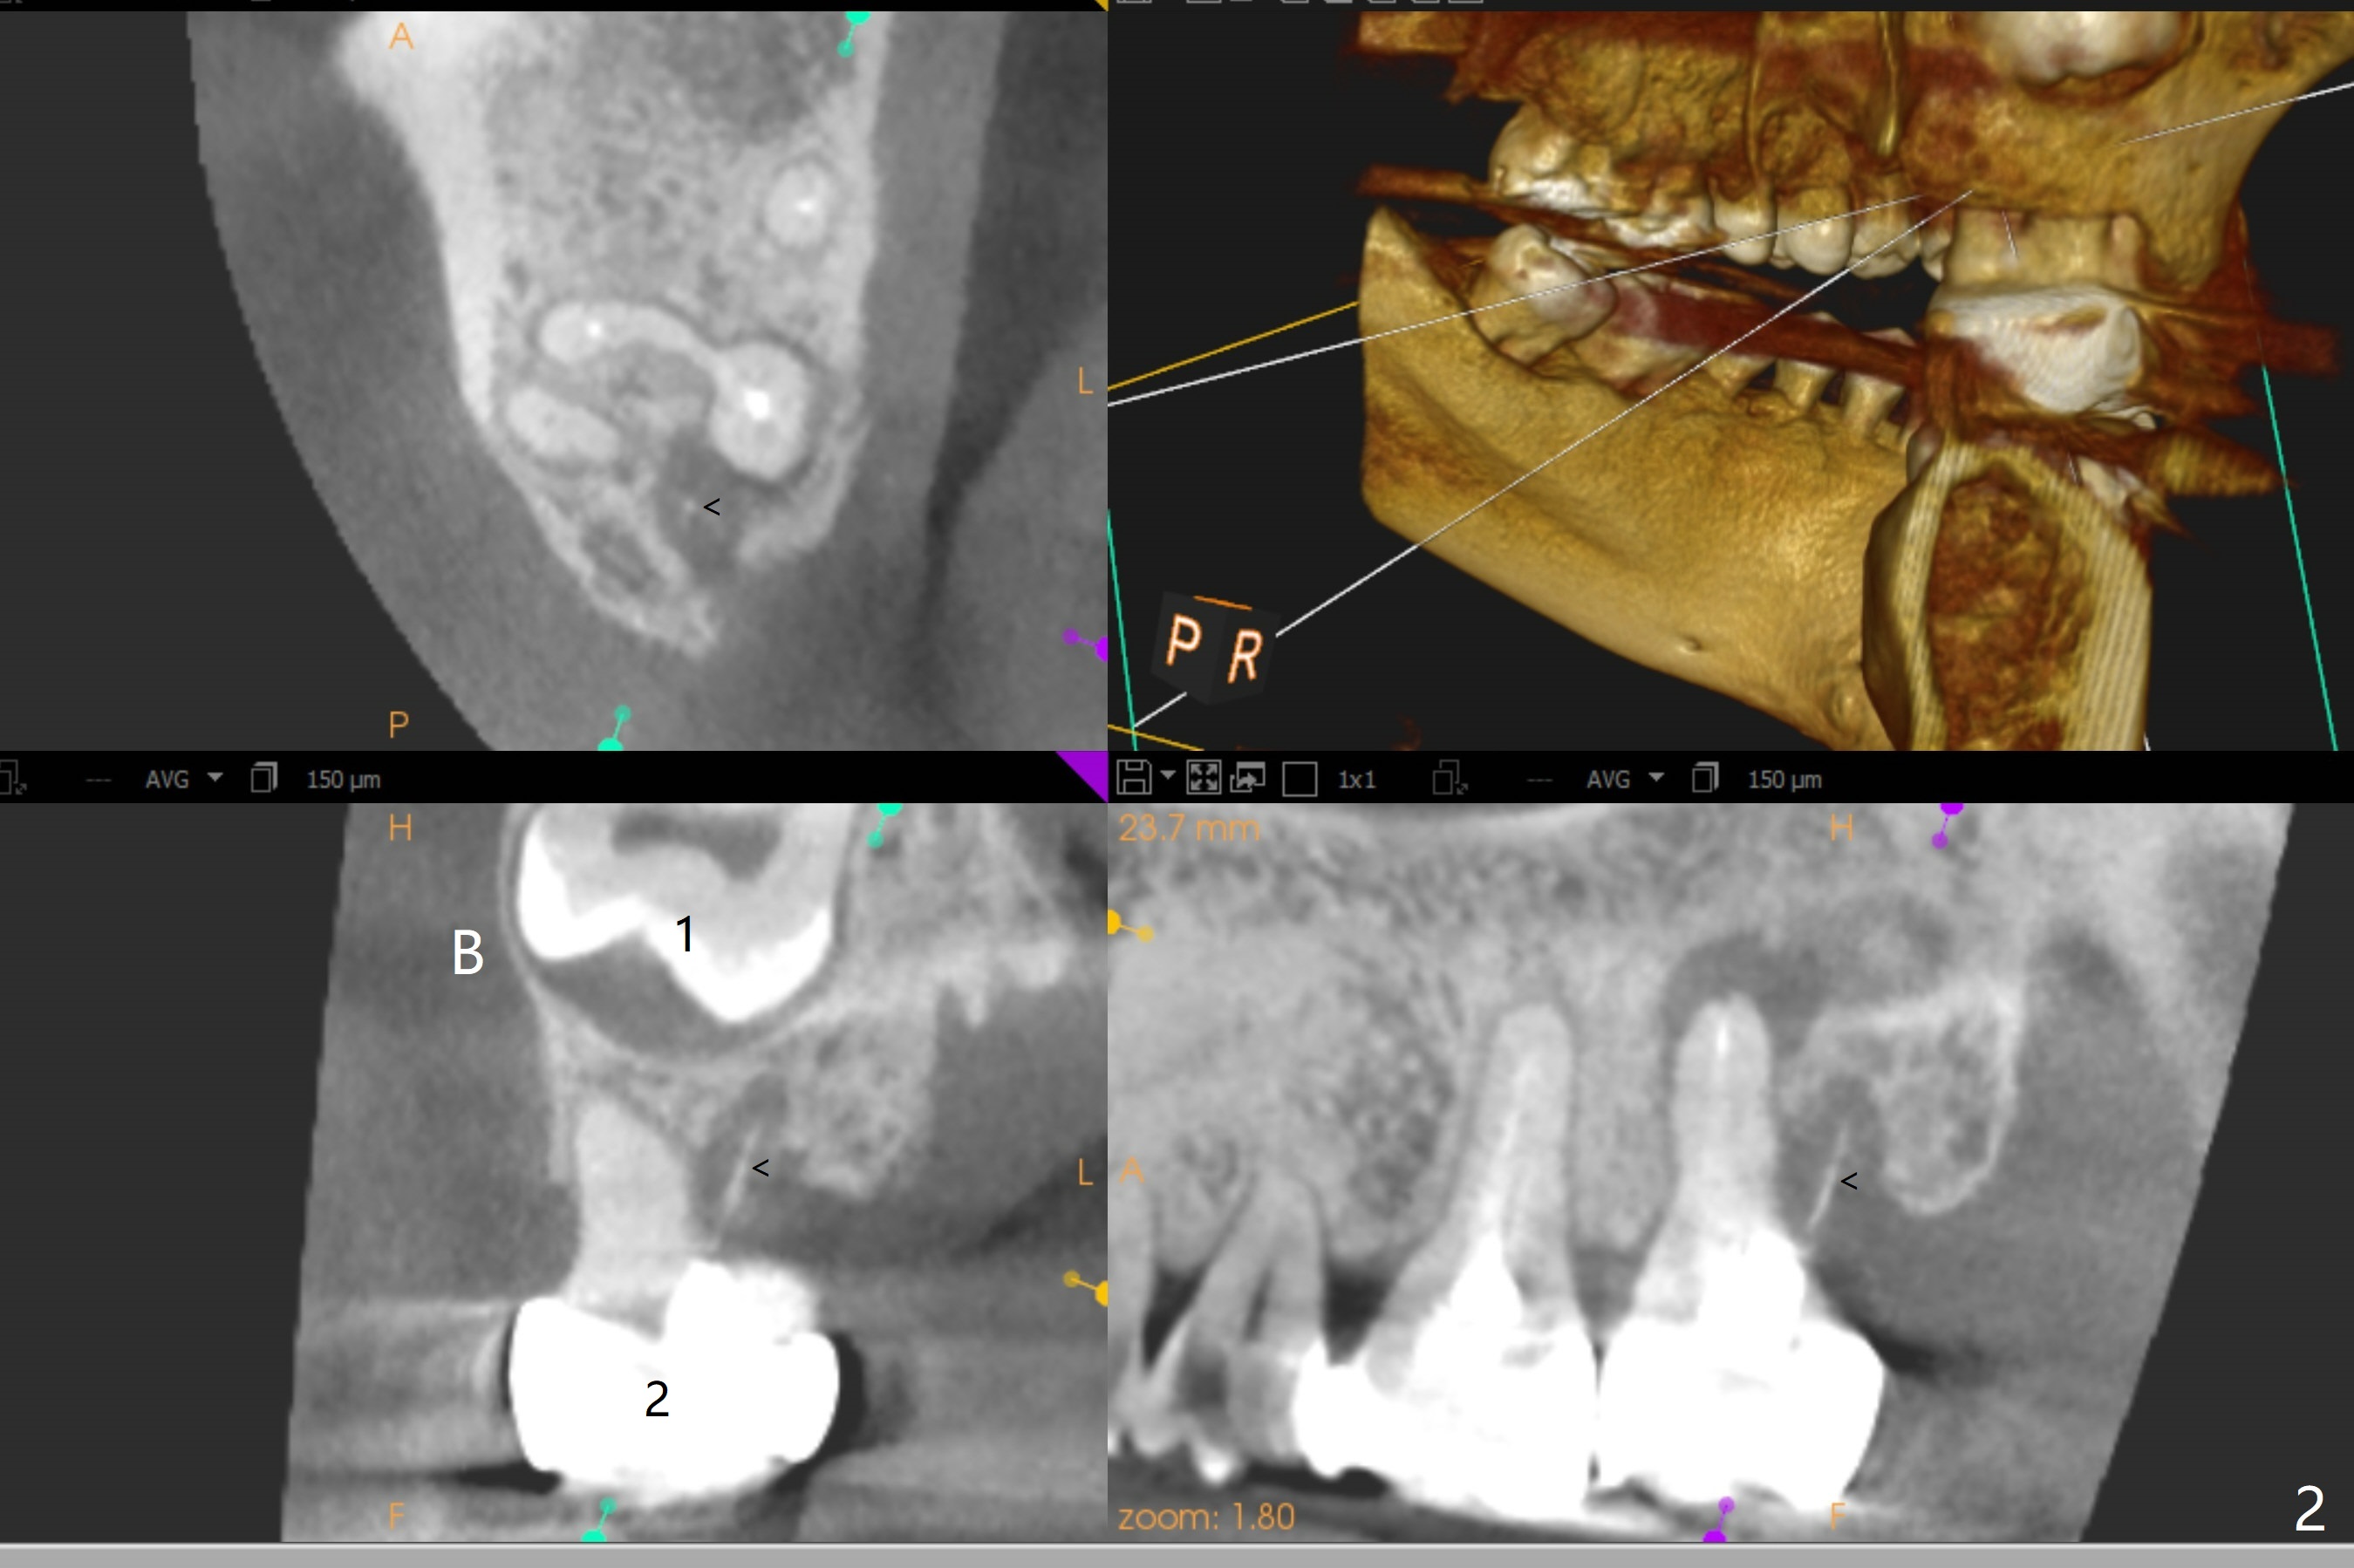

A 38-year-old woman returns to clinic with severe pain in the upper right 2nd molar (Fig.1), requesting immediate extraction. Endo consultation confirms nonsalvageability with gutta percha sticking out of the distobuccal root (Fig.2 arrowheads (B: buccal)). She would like to have an implant. What is the treatment plan? In fact the tooth #2 has been extracted with socket preservation.

The socket of #2 heals 13 days postop; it appears that the bone graft remains in place (Fig.7,8 *). The patient is instructed to return in 3-4 months for impression and CT for guide. The socket heals 4 months postop (Fig.9,10). She plans to have implant next year, since she wants to add another insurance. The patient returns for implant without removal of the third molar 2 years 4 months post socket preservation (Fig.11). A 5x7.3 mm implant can be placed without invading the sac of the impacted third molar (Fig.12). In fact the lab has a better plan. A lump of bone forms in the previous socket 1 year 4 months postop (Fig.13 *). The ridge is wide and dense (Fig.14). A narrow implant placed oblique could be longer (Fig.15), as compared to a wide, short one (Fig.12).